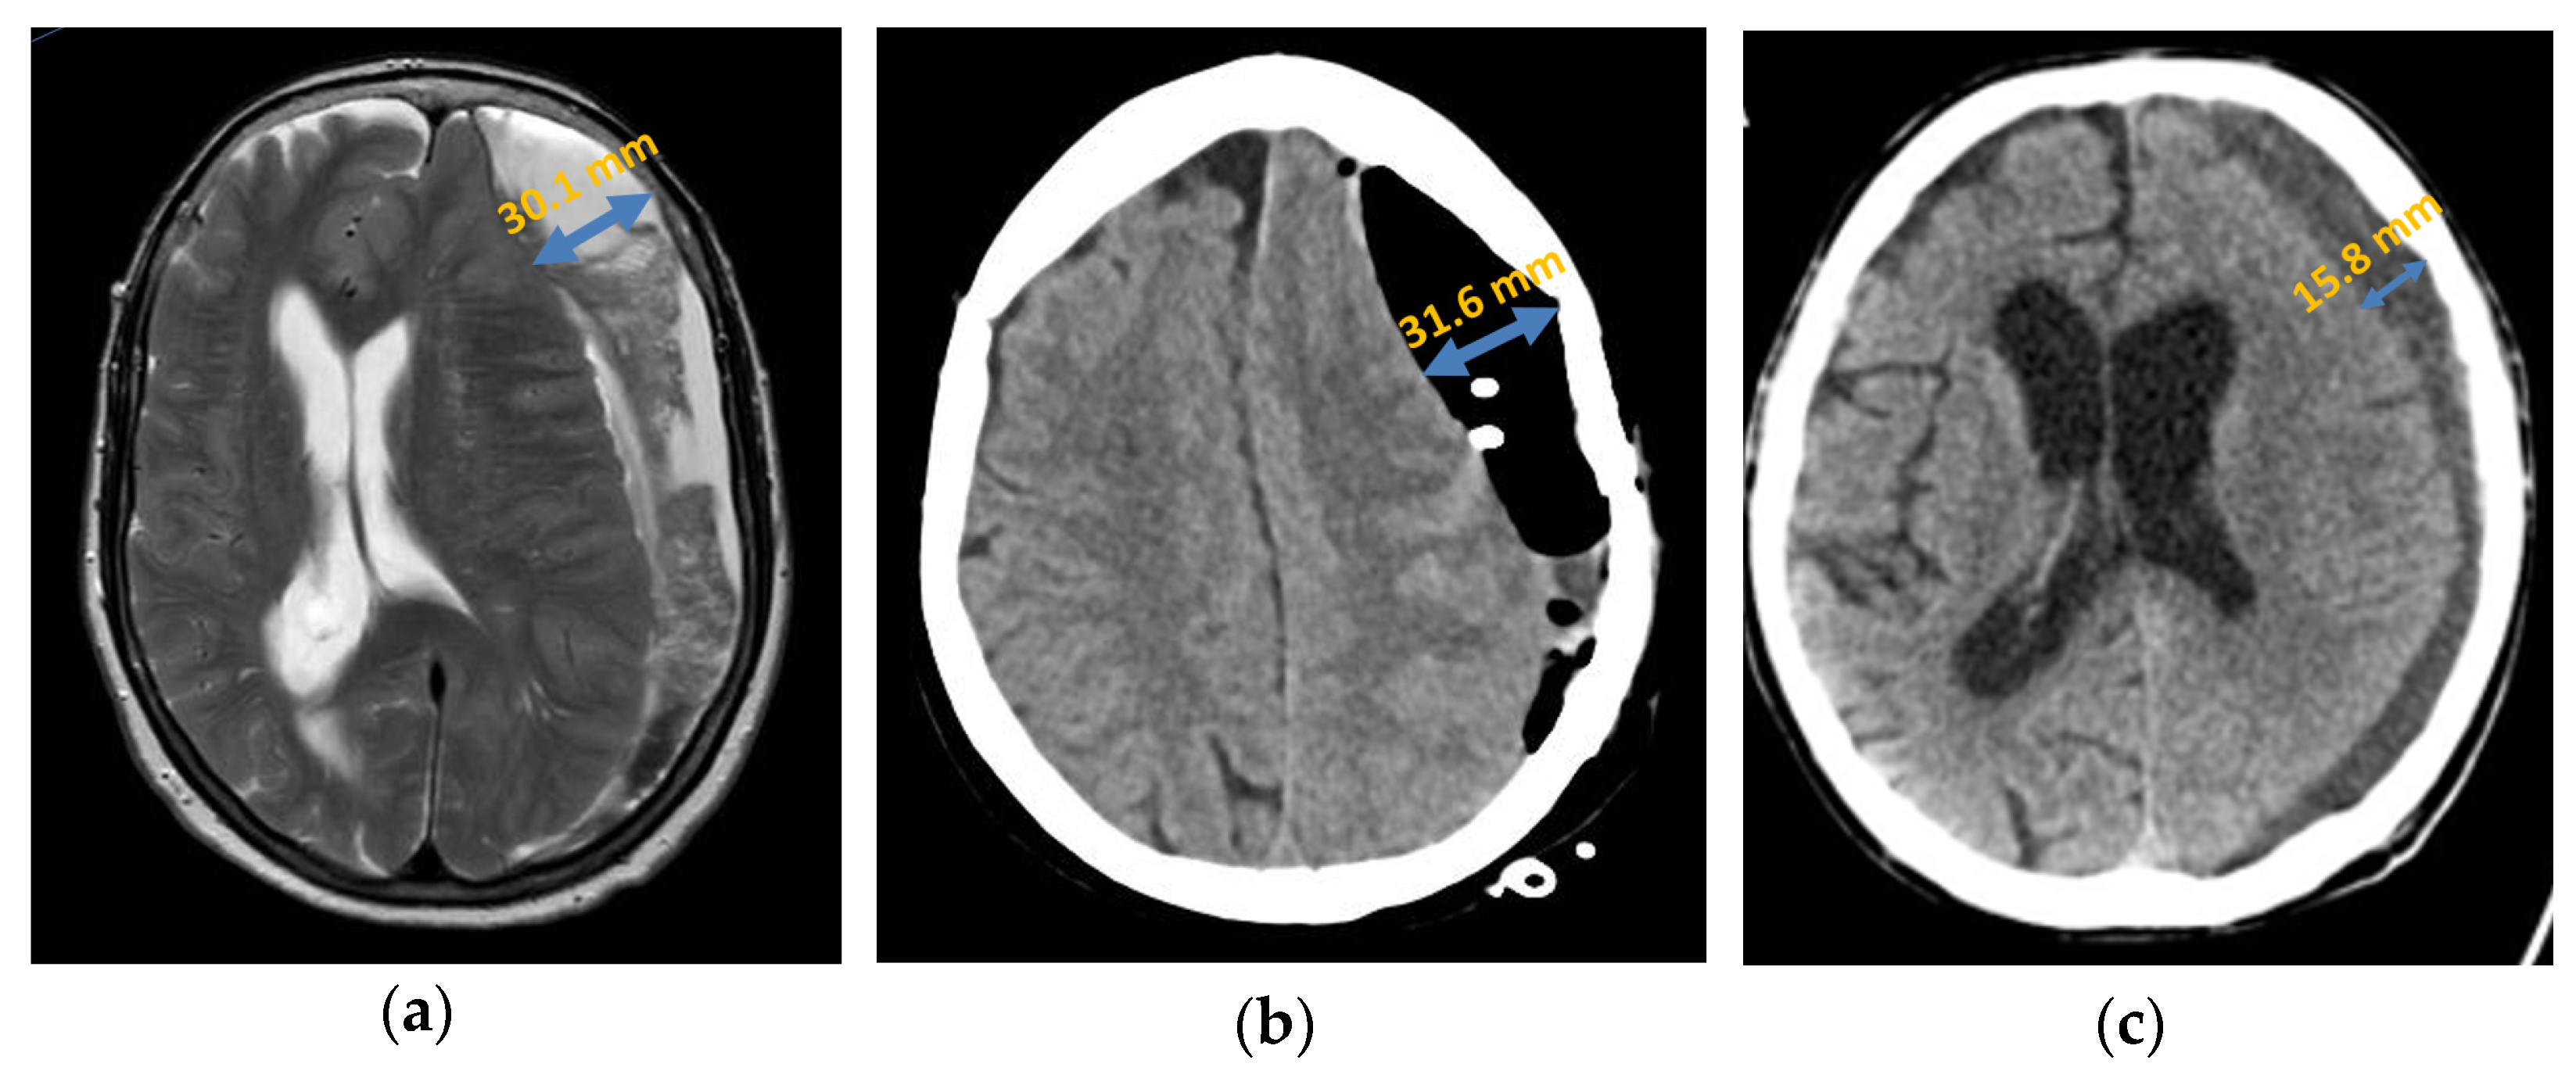

Figure 2.

Chronic subdural haematoma extended over both hemispheres: (a) preoperative presentation in axial CT; (b) postoperative presentation in axial CT.

In the patient group in which a recurrence occurred, the subdural haematoma extended over the entire affected hemisphere in 56.57% (n = 17), the fronto-parietal localisation in 33.33%, (n = 10), and the frontal localisation in 10.00% (n = 3). In the group of patients without a recurrence, 40.00% (n = 24) showed an extension over the entire hemisphere (16.56% lower than in the recurrent group of patients), 26.67% (n = 16) the fronto-parietal localisation, and 20.00% (n = 12) the frontal localisation. Furthermore, in two cases (3.33%), there was a parietal localisation and in one case (1.67%) a parieto-occipital localisation (Figure 3). However, the Fisher–Freeman–Halton exact test showed localisation was not a statistically significant prognostic factor for the risk of recurrence (p-value = 0.28).